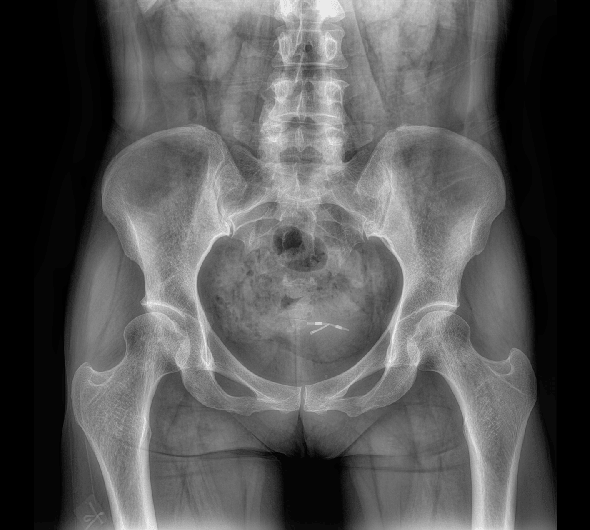

原厂优质影像链,搭载直接生长式碘化铯非晶硅平板,带来更加清晰锐利的图像效果。